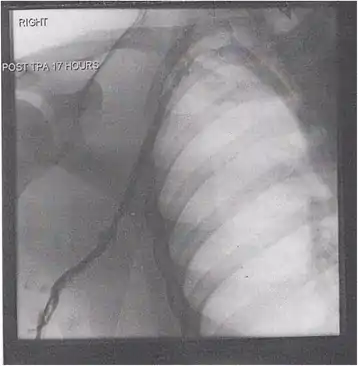

Thrombolysis is the injection of an enzyme into the veins to dissolve blood clots, and while this treatment has been proven effective against the life-threatening emergency clots of stroke and heart attacks, randomized controlled trials[139][140][141] have not established a net benefit in those with acute proximal DVT.[5][142] Drawbacks of catheter-directed thrombolysis (the preferred method of administering the clot-busting enzyme[5]) include a risk of bleeding, complexity,[lower-alpha 12] and the cost of the procedure.[125] Although, while anticoagulation is the preferred treatment for DVT,[125] thrombolysis is a treatment option for those with the severe DVT form of phlegmasia cerula dorens (bottom left image) and in some younger patients with DVT affecting the iliac and common femoral veins.[12] Of note, a variety of contraindications to thrombolysis exist.[125] In 2020, NICE kept their 2012 recommendations that catheter-directed thrombolysis should be considered in those with iliofemoral DVT who have "symptoms lasting less than 14 days, good functional status, a life expectancy of 1 year or more, and a low risk of bleeding."[138]

A mechanical thrombectomy device can remove DVT clots, particularly in acute iliofemoral DVT (DVT of the major veins in the pelvis), but there is limited data on its efficacy. It is usually combined with thrombolysis, and sometimes temporary IVC filters are placed to protect against PE during the procedure.[143] Catheter-directed thrombolysis with thrombectomy[141] against iliofemoral DVT has been associated with a reduction in the severity of post-thrombotic syndrome at an estimated cost-effectiveness ratio of about $138,000[lower-alpha 13] per gained QALY.[144][145] Phlegmasia cerulea dolens might be treated with catheter-directed thrombolysis and/or thrombectomy.[19][143]

In DVT in the arm, the first (topmost) rib can be surgically removed as part of the typical treatment when the DVT is due to thoracic outlet syndrome or Paget–Schroetter syndrome. This treatment involves initial anticoagulation followed by thrombolysis of the subclavian vein and staged first rib resection to relieve the thoracic outlet compression and prevent recurrent DVT.[146]